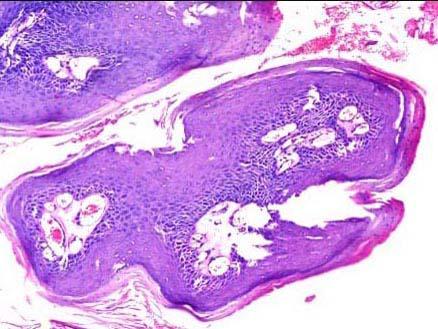

问题 患者,男,8岁,进行性声嘶4天,喉镜见声门区乳头状肿物三枚,淡红色,约0.2cm×0.5cm×0.6cm至1.4cm×1cm×0.8cm,基底部较宽,摘除活检,镜下如图所示,该患儿的正确诊断是 ( )

选项 A.声带小结 B.喉血管瘤 C.喉神经纤维瘤 D.喉纤维瘤 E.喉乳头状瘤

答案 E